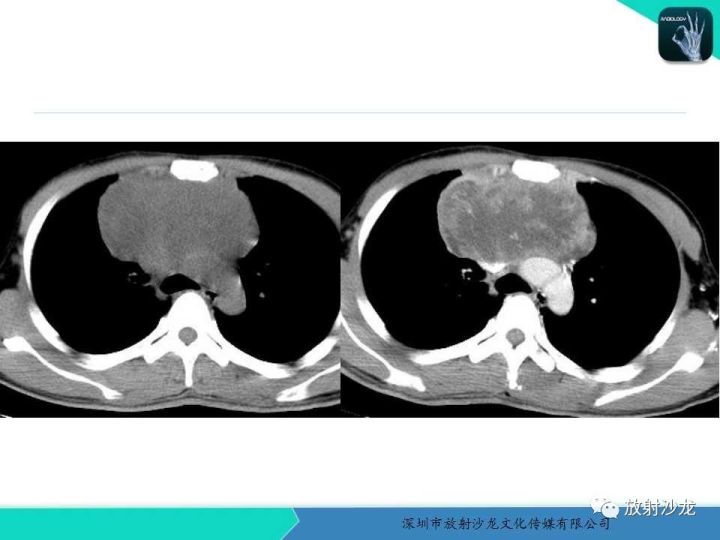

【病例】纵隔卵黄囊瘤1例CT影像表现